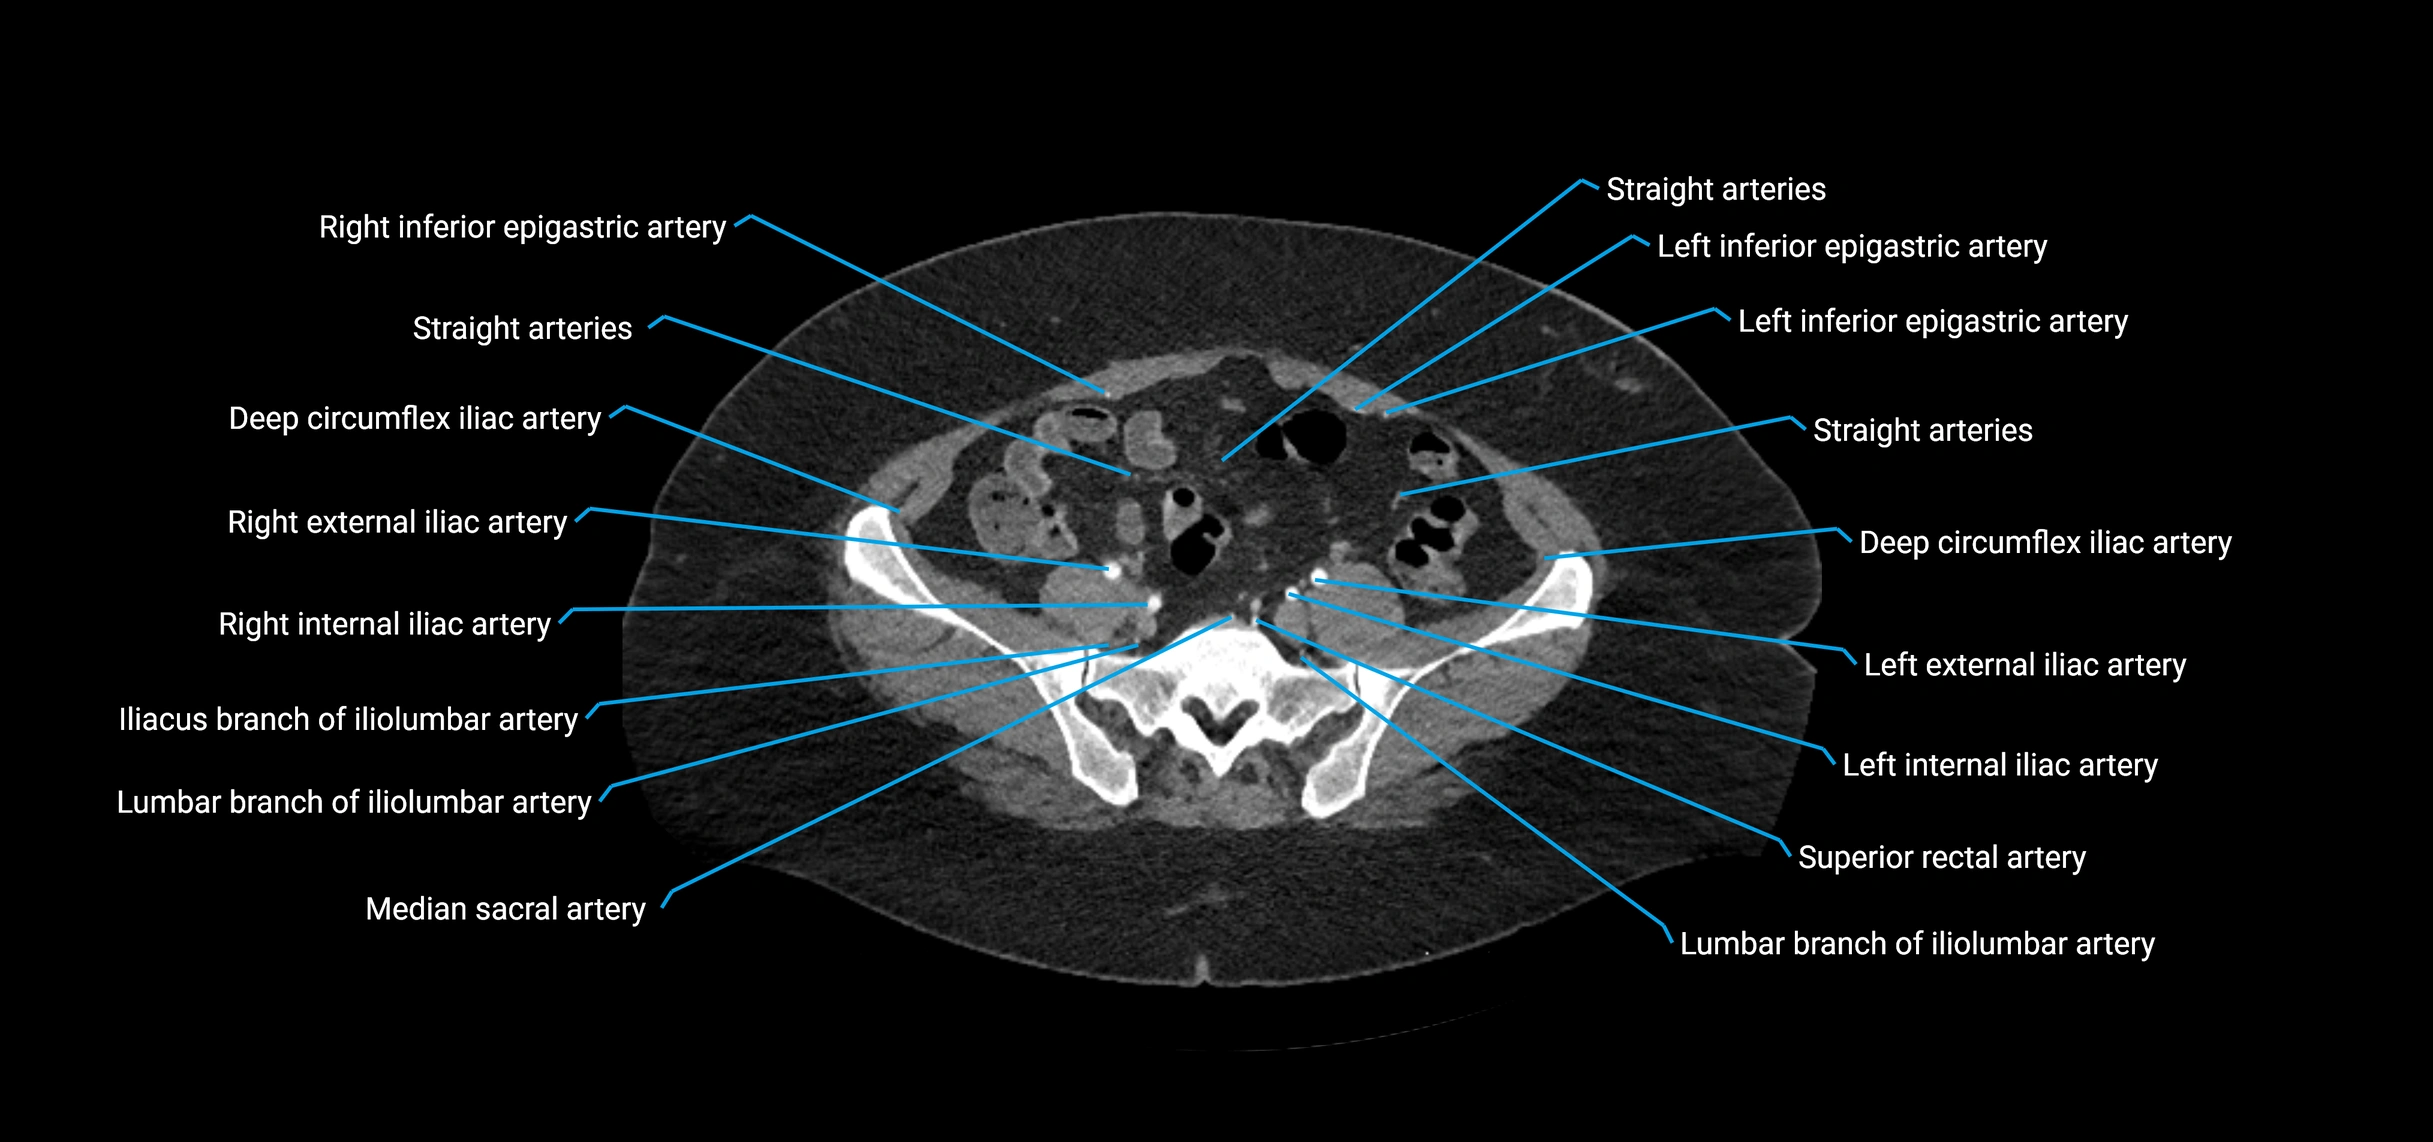

• Parietal branches: inferior phrenic arteries, lumbar arteries, median sacral artery

• Terminal branches: right and left common iliac arteries

Contrast-enhanced CT (CTA):

• Gold standard for abdominal aortic imaging

• Provides excellent detail of lumen, wall, aneurysm, thrombus, and branch vessels

• Multiplanar and 3D reconstructions help in aneurysm measurement, stent graft planning, and dissection evaluation